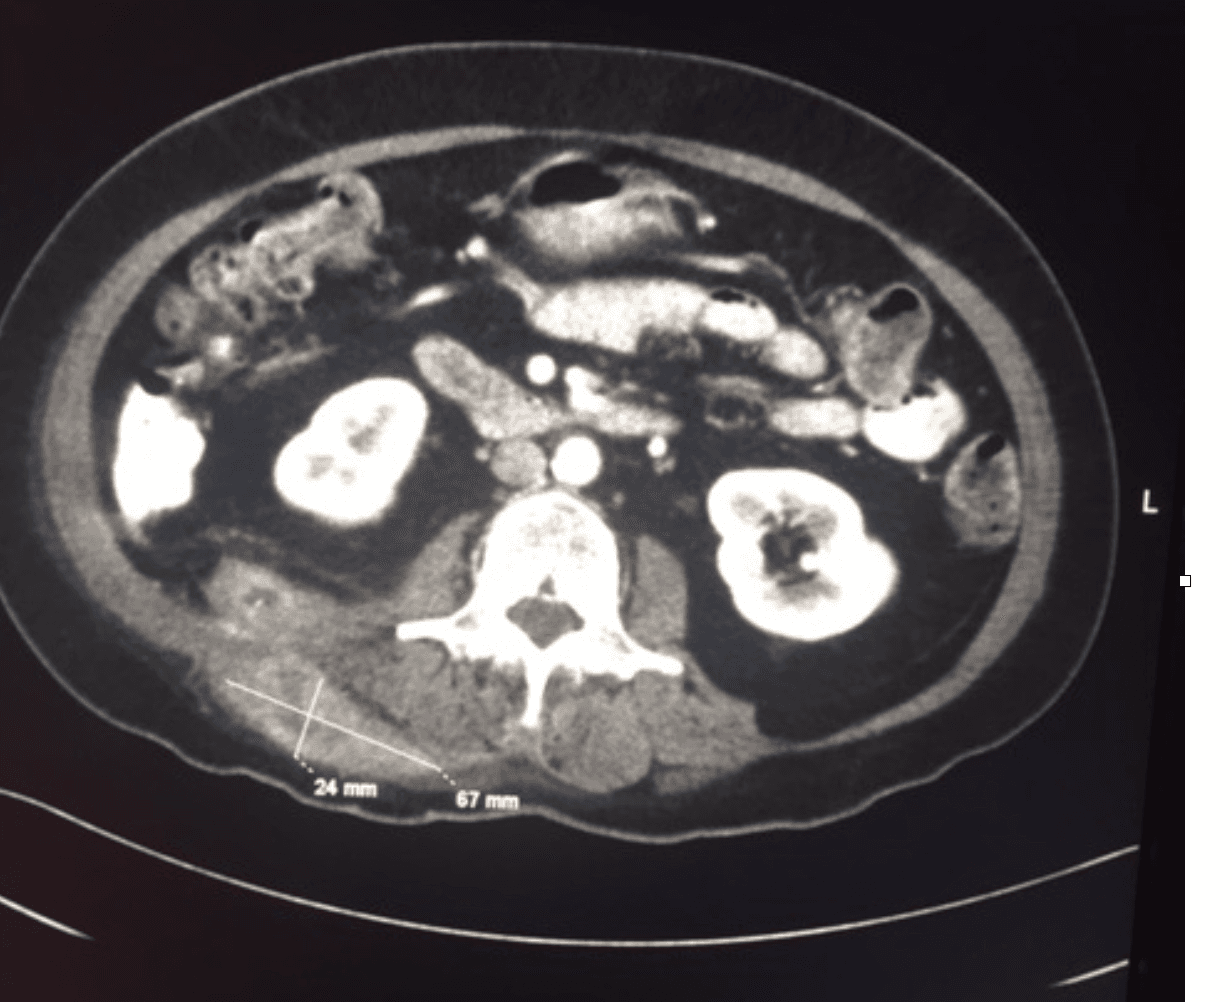

CT and tissue pathology were obtained because malignancy was initially suspected. Imaging showed an infiltrative soft-tissue process with mass-like appearance. Histopathology demonstrated sulfur granules with branching filamentous gram-positive organisms, consistent with actinomycotic infection.